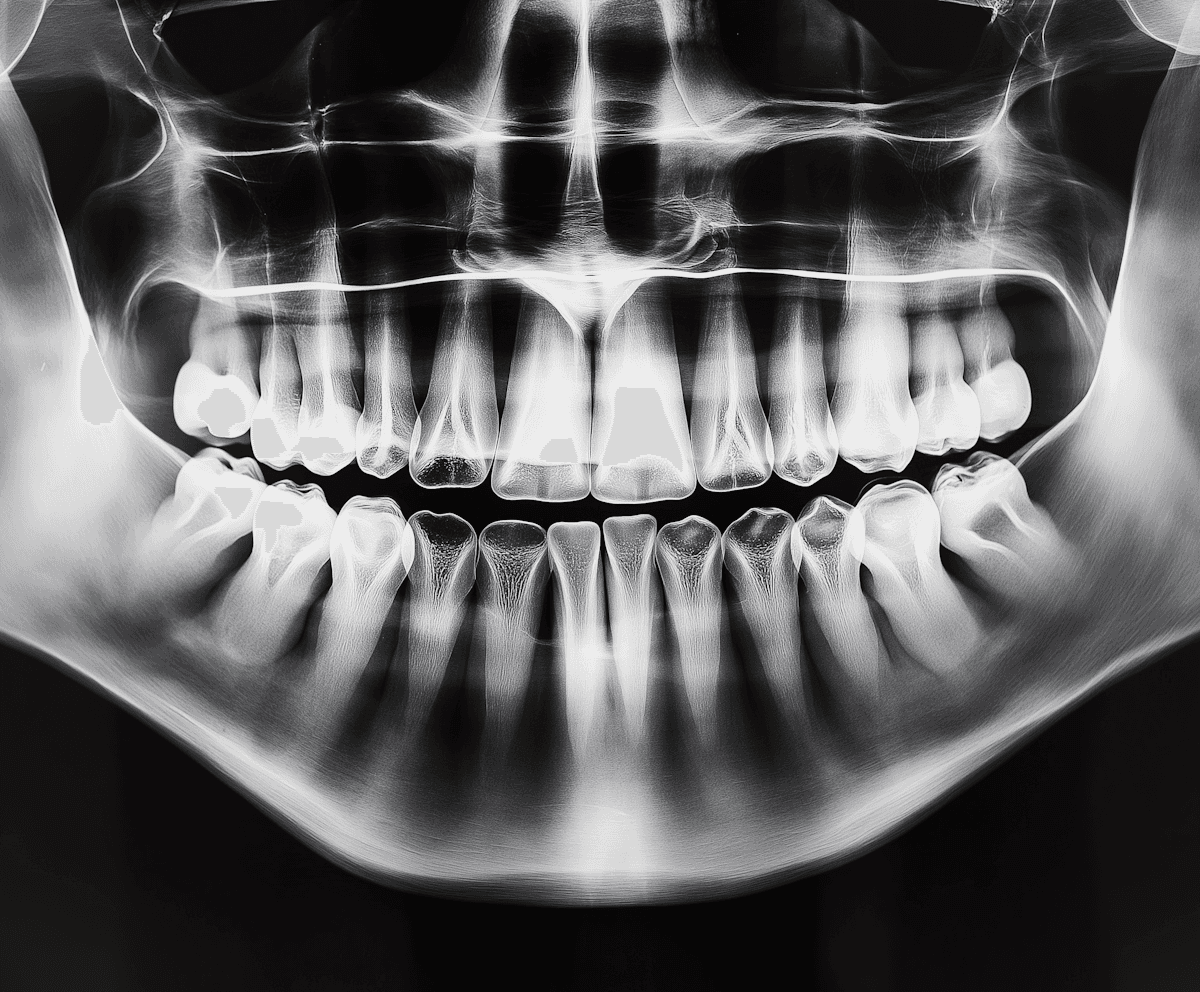

Book your appointment today for personalized dental care in a welcoming environment. Let us help you achieve a healthier, more confident smile.